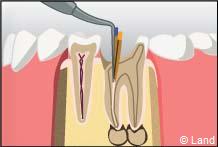

2° Il doit ensuite mettre en forme le canal afin de pouvoir réaliser l’obturation canalaire, le plus souvent à l’aide de gutta-percha chauffée ou froide permettant d’obtenir une étanchéité de bonne qualité afin de prévenir toute ré-infiltration par des bactéries et d’assurer sur le long terme la conservation d’une dent assainie. S’il y avait une lésion infectieuse au bout de la dent, celle-ci guérira, si elle n’est pas déjà trop avancée.